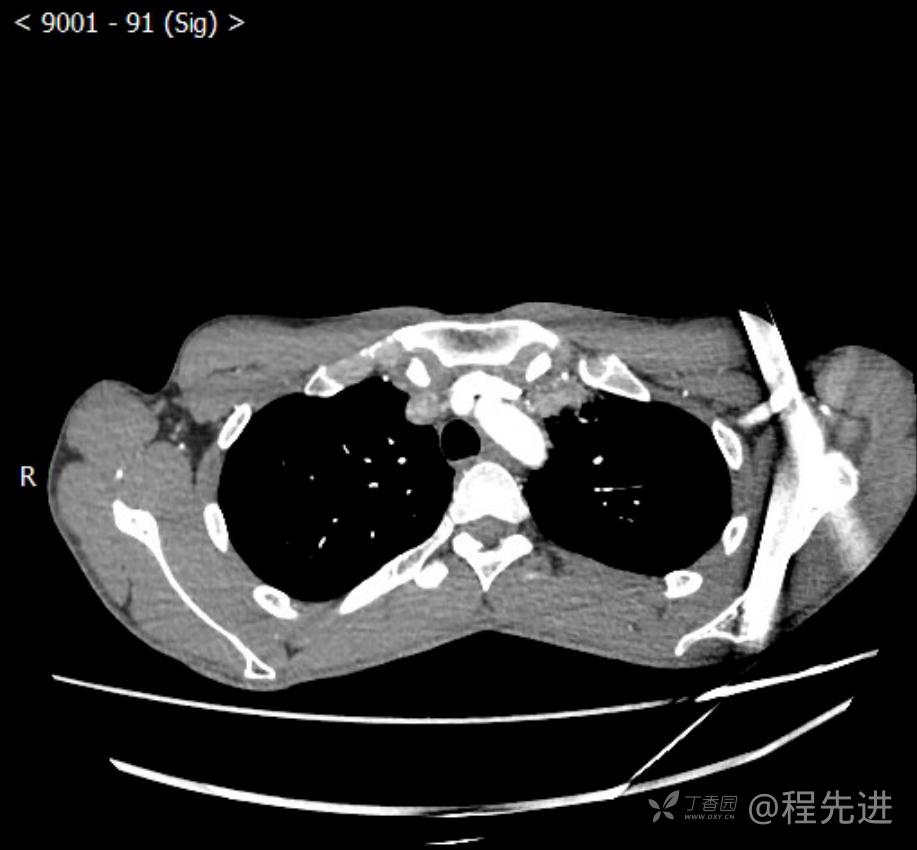

主诉:反复咳嗽1月,发现“纵隔”占位半月,乏力10余天。

现病史:患者1月前无明显诱因出现咳嗽,以夜间为著,伴有少量白痰,无发热,无胸痛、咯血,无痰中带血,未予重视,半月前外院行胸部CT检查发现“左前上纵隔”占位,未予进一步检查及治疗。近10余天自觉乏力,逐渐加重。